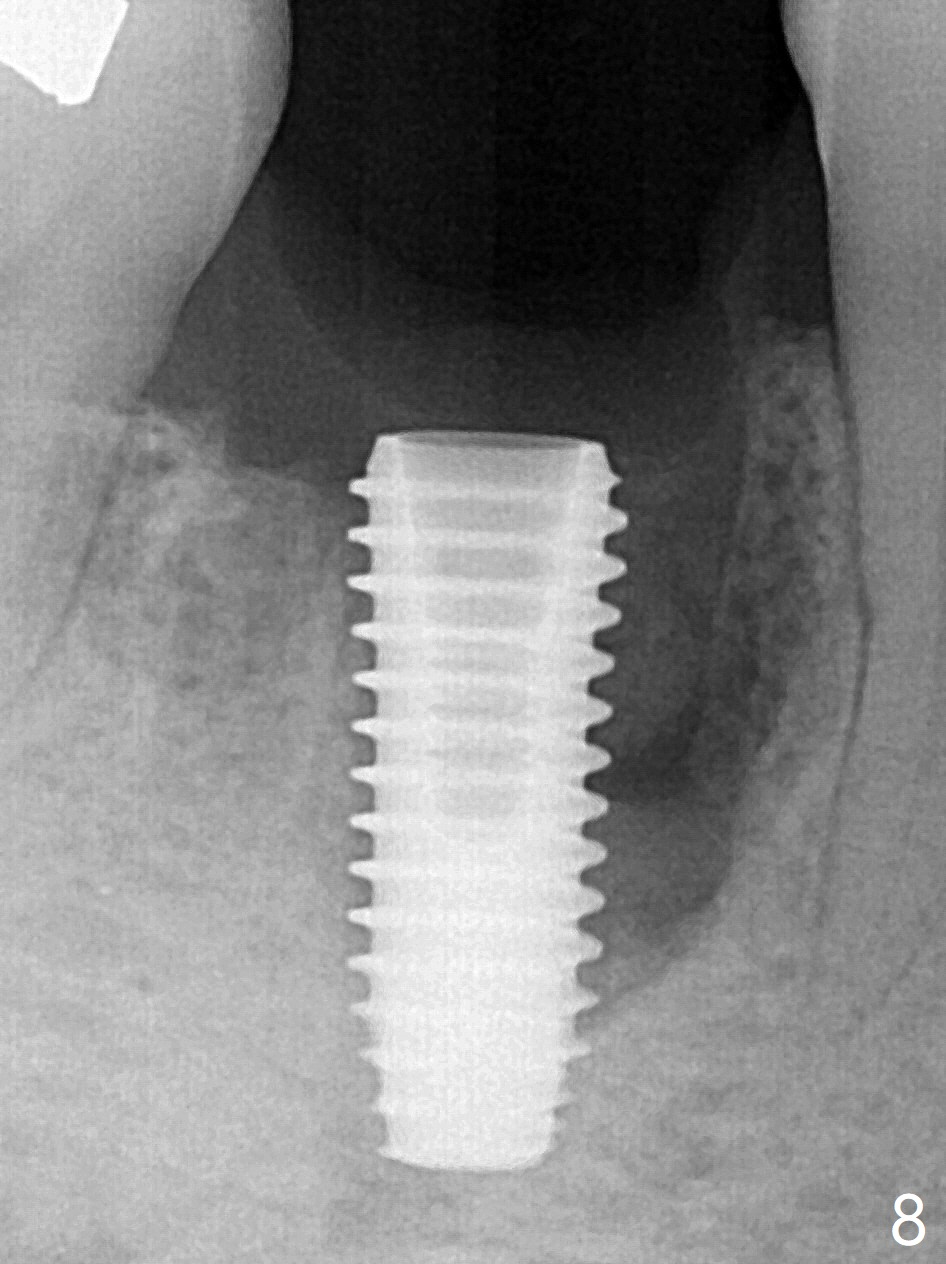

Preop oral Amoxicillin seems to be associated with reduction in the buccal and lingual (Fig.3 arrow) fistulae at #30, but there is mesiobuccal swelling (Fig.1 *) with 7 mm pocket (Fig.2). Osteotomy is initiated in the middle of the septum (Fig.3-5 S). As the osteotomy increases, it shifts mesially (Fig.6 arrow). Guided surgery is able to reduce shifting. A 5x13 mm implant is not seated completely (Fig.7) apparently due to osteotomy shifting. After removal of the bone from the osteotomy distally, the implant remains unseated with lower torque value (Fig.8). Following reuse of the 4.3 mm drill deeper by 1-2 mm, the implant is seated to a satisfactory depth (Fig.9 with increase in torque to 50 Ncm) with placement of Vera Graft (*) and a 7.5x4(3) mm abutment. After a second round of allograft placement (Fig.10 *), the implant is found to be 4 mm from the IAC. At the later stage of osteotomy, the coronal end of the septum is destroyed with loss of osteotomy depth landmark. It is apparent that the soft tissue landmark may be more reliable. The implant threads appear to be covered by the bone graft 3.5 months postop (Fig.11). The abutment is changed to 6.5x5(3) mm one before impression with minor margin prep. The bone density seems to increase 5 months postop, i.e., immediately post cementation (Fig.12) and 10 months postop (5 months post cementation (after retightening abutment), Fig.13 (*)). Periimplantitis develops mesiobuccally, consistent with bone loss 1 year 7 months post cementation (Fig.14 *); the implant seems to have been buccally placed. Bone graft is necessary with PRF or GEM21S if the vein is small and 6-month membrane with a hole around a 7.5x4(4) cemented abutment for easy wound closure. Take 5x5 CM CBCT to determine which wall has defect, buccal or lingual. Check mesial contact. If so, remove the crown, reseat the abutment (possible incomplete seating) and re-impress after bone graft.